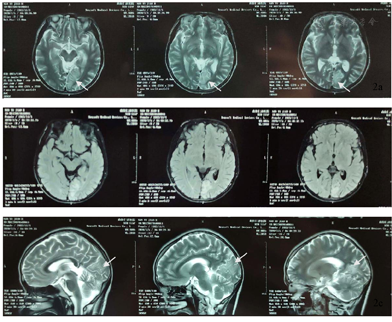

患者,女性,37岁,主因"间断抽搐发作36余年,加重5月余"于2020年11月24日就诊于河北医科大学第二医院神经内科。患者于6月龄时出现抽搐发作,表现为双眼向右上偏斜,四肢抽搐,伴意识不清,呼之不应,持续约数小时缓解。后此症状间断发作,表现同前,每次共3 h左右,发作频率约1次/20 d,共发作3次后未再发作。8月龄时出现发作性肢体活动障碍,表现为哭闹时仅一侧肢体活动,意识清楚,偏瘫侧肢体软,左右侧肢体交替发作,单侧偏瘫持续3天左右交替至另一侧,每次共持续1周左右,发作频率约半个月1次,就诊于当地医院,诊断为"低钙抽搐",给予补钙治疗,症状未见明显好转。1岁半时就诊于北京数家医院,于首都医科大学宣武医院完善头颅CT检查未见明显异常(具体不详),予以口服药治疗(具体不详),服用完后自行停药。后间断就诊于当地医院,诊断为"癫痫",15岁左右开始口服抗癫痫药物(具体不详)。11年前(26岁时)口服卡马西平0.2 g、2次/d,出现发作性肌张力障碍,表现为双上肢伸直,双手腕屈曲外旋,偶伴头眼右偏,意识清楚,为成簇发作,约半个月1簇,3~5 d/簇,数次/d,每次持续约数分钟,月经前或情绪不稳定时易发作;交替性偏瘫发作症状逐渐演变为发作时偏瘫侧肢体伴有强直性肌张力障碍,右侧肢体发作时症状常较左侧重。逐渐停用卡马西平(共服用数月),上述症状仍间断发作,发作表现及频率同前,就诊于北京数家医院,于北京三博脑科医院完善头颅核磁共振、24 h视频脑电图、48h视频脑电图和脑磁图等检查,家属回忆视频脑电图示未见癫痫样放电,头颅核磁共振示有病灶,脑磁图示病灶位置较深不宜手术(因检查结果及报告丢失,具体不详),诊断为"运动障碍性疾病",予以口服美多芭治疗,症状未见好转,数月后自行停用。此后数年间患者除交替性偏瘫发作、肌张力障碍发作外间断于清醒状态下出现全面性强直-阵挛发作2次,发作前有头痛先兆,每次持续约30 min。入院5个月余前患者于清醒状态下突然出现右侧肢体抖动,伴头眼右偏,口角向右侧偏斜,意识丧失,伴流涎,持续约数小时,就诊于当地医院查头颅MR示左侧颞顶枕叶病变,性质待定,后此症状间断发作,偶伴小便失禁,发作前有恶心、呕吐等先兆,发作频率约1次/周,患者逐渐无法自行行走;入院3个月前患者发作形式变化为右手右脚抖动,伴右侧面肌、嘴角抽搐,每次持续约数小时,频率约1次/10 d。现患者口服"丙戊酸钠0.4 g、3次/d,左乙拉西坦每早0.75 g,每晚0.5 g"。个人史:足月顺产,系第一胎第一产,其母亲诉其出生受冻史;运动发育迟缓,6岁会走路;未婚未育,父母及2个妹妹体健。既往史:偏头痛病史20余年,未予诊治;甲状腺功能亢进症病史5年余,口服甲巯咪唑片治疗。月经史、家族史无特殊。入院神经系统查体示神清,智力发育、理解力较差,双瞳孔正大等圆,对光反射稍迟钝,双手肌张力障碍样姿势,右侧肢体肌张力稍高,四肢腱反射(+++),双侧巴宾斯基征(-),余查体不合作。

ATP1A3基因突变可导致生命早期严重癫痫[8]。约半数AHC患者合并癫痫,且多为耐药性癫痫,癫痫发作可与偏瘫发作同时发生或独立出现[2],癫痫类型和癫痫发作类型多样,癫痫发作甚至癫痫持续状态(SE)可以发生在其他类型的AHC发作之前,通常始于新生儿期[9]。携带E815K突变患者通常表现为更严重的AHC表型,癫痫和SE的发生率更高[2,9]。本例患者具备多种癫痫发作类型,常独立出现,多表现为SE,抗癫痫药物反应欠佳。AHC患者影像学表现通常是正常的,少数可出现大脑或小脑萎缩[9,10,11],值得注意的并遗憾的是,本例患者入院前2次于癫痫发作后行头颅MR检查示左侧颞顶枕叶病变,入院后复查头颅MR提示该病变呈可逆性,脑萎缩加重,线粒体环基因及核基因检测未发现突变,最终我们未能明确其性质及原因。国外1项队列研究中观察到1例患者在SE后24 h内进行MRI检查,出现右侧顶叶内侧T2加权液体反转恢复(FLAIR)序列灰质信号增强,并与发作期视频脑电图(EEG)异常及症状学相符,这与本例患者类似[9]。此外该研究还显示AHC患者EEG异常和癫痫样放电的发生率随着监测次数的增加而增加[9]。